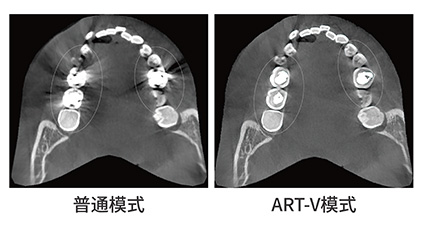

ART-V去伪影技术

vatech已经打破了许多牙科惯例。人们一直认为,金属伪影会导致劣质的影像质量,然而这问题始终无法解决。现在ART-V可以有效减少金属伪影,使得图像质量更有诊断价值。